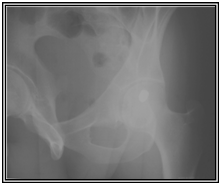

A 32 old male presented with a single gunshot wound to the right suprapubic area, with no exit. Radiographs revealed a bullet that appeared to be lodged in the left hip joint (Figures 1) A CT scan (Figures 2) and cystogram showed no associated injuries, with the bullet tract entering the quadrilateral surface of the left hip and the bullet buried in the posterior acetabular wall.

Figure 1 Radiographs at first presentation showing a bullet that appeared to be lodged in the left hip joint.